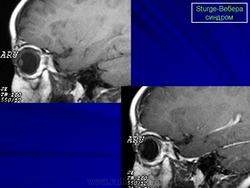

Магнитная резонансная томография пациента с болезнью Штурге - Вебера

Магнитная резонансная томография пациента с болезнью Штурге - Вебера